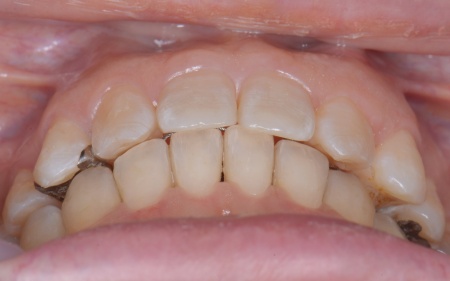

50代女性 インプラント・矯正・被せ物治療で見た目と噛み合わせを改善した症例

「以前治療した左下奥歯が思うように噛めない。また、矯正治療を受けた前歯でうまく噛めない」とご相談いただきました。

さらに患者様は全体的に歯並びや噛み合わせに問題があり、特に上下の前歯は噛んだ際に隙間ができ食べ物を噛み切りにくい状態です。

さらに全体の噛み合わせを改善するため矯正治療を並行して行うこと、右上下奥歯の合わなくなった被せ物には矯正終了後に新しく作り直すこととしました。

④矯正終了後に右上下奥歯の合わなくなった被せ物を除去し、自然な白さで強度もあるジルコニアセラミッククラウンを装着する。

最後に装着したジルコニアセラミッククラウンが歯に合っているか、噛み合わせに問題がないかを確認し、治療を終了しました。